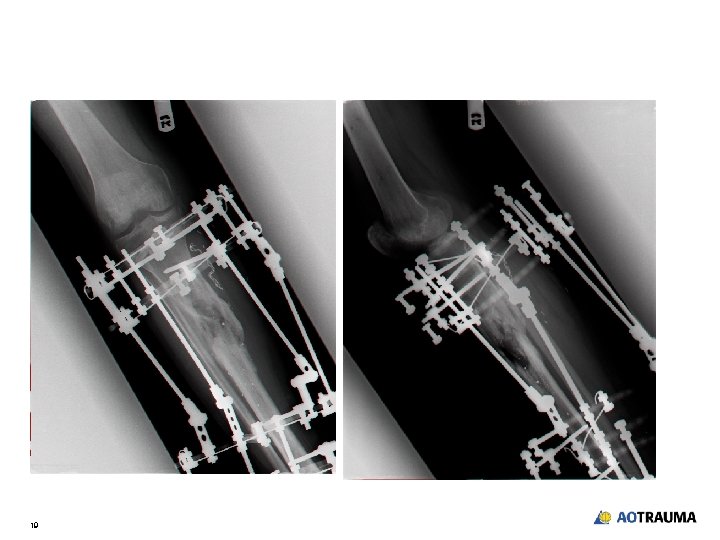

Follow-up over 18 weeks • Soft-tissue healing but a small intermittent sinus continues over anterior medial side of leg • When patient receives antibiotics swelling and sinus resolve • Plan - Continue with correction as regenerate will “burn out the infection” 10

18 weeks 11

Rationale for waiting in the face of continued infection • • • Fixation stable Fracture showing signs of healing Patient not threatened by sepsis • Plan - Wait for fracture to heal then deal with infection 12